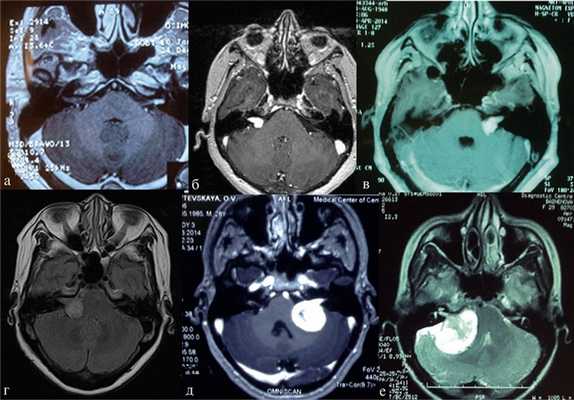

Рис. 2.Классификация неврином слухового нерва по M. Samii. а — Т1 — интрамеатальная опухоль (рис. 2, a); б —Т2 — интра-экстрамеатальная опухоль; в — Т3а — опухоль заполняет мостомозжечковую цистерну; г —Т3b — опухоль распространяется до ствола головного мозга; д —Т4а — опухоль вызывает компрессию ствола; е —Т4b — опухоль грубо деформирует ствол мозга и IV желудочек.